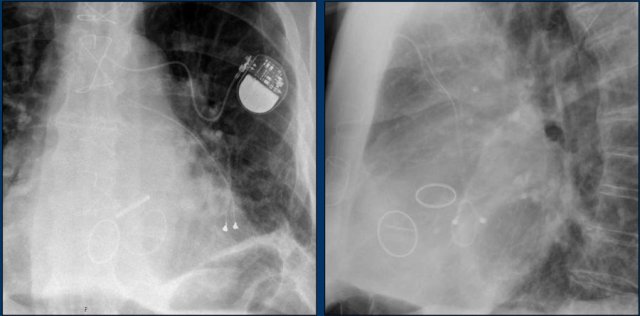

The findings are:

• Two epicardial leads connected to pacemaker

• ICD

• two leads to right ventricular apex

• one lead contains two shock coils

• tricuspid valve (arrows)

• mitral valve